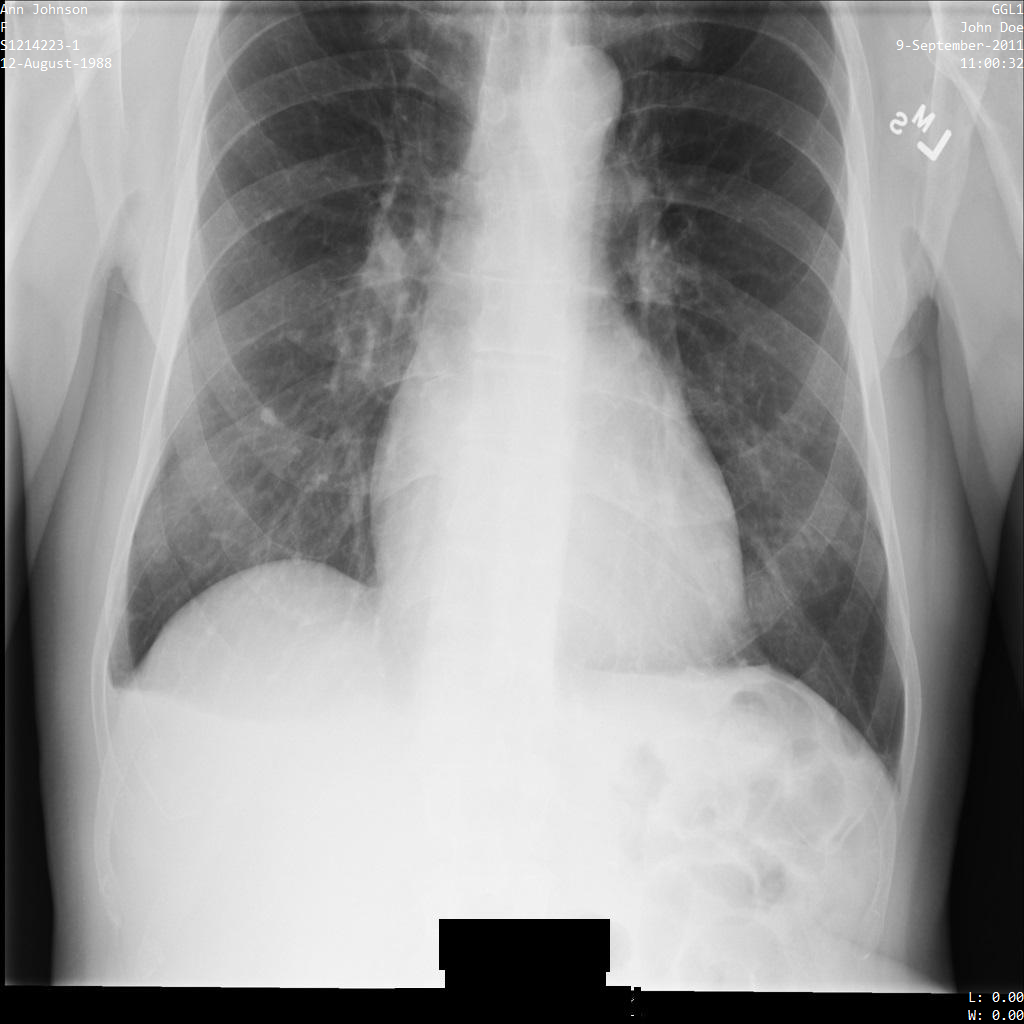

Chacune des sections suivantes fournit des exemples d'anonymisation de données DICOM à l'aide de différentes méthodes. Une sortie de l'image anonymisée est fournie avec chaque échantillon. Chaque exemple utilise l'image d'origine suivante comme entrée :

xray_original

Vous pouvez comparer l'image de sortie de chaque opération d'anonymisation à cette image d'origine pour voir les effets de l'opération.